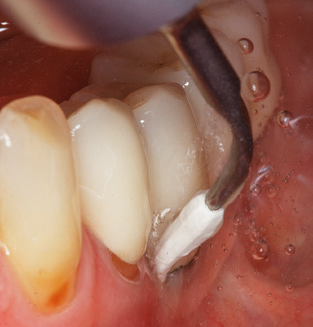

Good illumination of the working field facilitates the process considerably. The system used by the authors achieves this thanks to a 5x LED ring integrated in the handpiece. Naturally, a range of working tips for different indications is also offered. A straight, universally employable tip is the basic instrument required for machine cleaning of natural teeth (Fig. 5a and b). Curved tips, which allow access to exposed furcations, are also available for hard-to-reach areas in the posterior region (Fig. 6).

Fig. 4: Flexible probes with millimetre markings are recommended for the probing of dental implants (e.g. Colorvue Kit PCV11KIT6, Hu­Friedy). – Fig. 5a and b: A straight working tip (1P, W&H Dentalwerk Bürmoos GmbH) is a suitable instrument for use on all natural teeth. – Fig. 6: Curved working tips (3Pr/3Pl, W&H Dentalwerk Bürmoos GmbH) lend themselves to the processing of difficult-to-reach areas of the tooth and root surfaces (e.g. furcations). – Fig. 7: The tapered, hexagonal implant cleaning tip (1I, W&H Dentalwerk Bürmoos GmbH) permits atraumatic and efficient cleaning of the crown and abutment surfaces. – Fig. 8: Titanium and carbon curettes are suitable instruments for the manual cleaning of the implant surfaces.